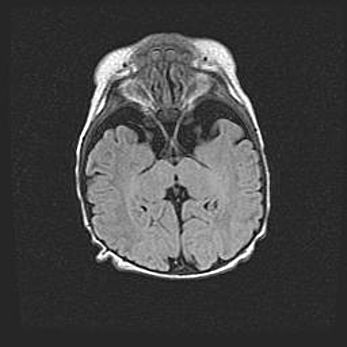

Лейкомаляция с кистозно-глиозной дегенерацией головного мозга.

Возраст: 2 месяца 25 дней

Вес: 6400 г

Окружность головы: 40 см

Срок гестации: 41 неделя

Лейкомаляцию относят к ишемически-гипоксическим повреждениям головного мозга, диагностируемым у новорожденных. При лейкомаляции в головном мозге обнаруживают очаги некроза, возникшие после тяжелой гипоксии и нарушения кровотока. В процессе морфогенеза очаги проходят три стадии: 1) развития некроза, 2) резорбции и 3) формирования глиозного рубца или кисты. Перивентрикулярная лейкомаляция (ПЛ) встречается примерно в 12% случаев среди новорожденных, обычно – у недоношенных детей, причем, частота ее зависит от массы, с которой младенец появился на свет. Наибольшее число малышей страдает лейкомаляцией, если масса при рождении 1500-2500 г.